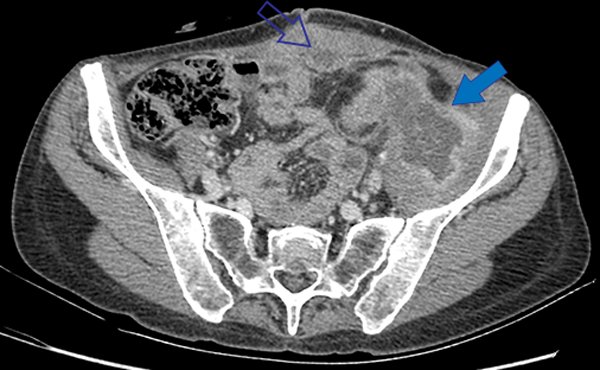

Se completó la valoración con una videocolonoscopía que evidenció sobre la unión descendente sigmoidea una lesión de aspecto velloso con abundante moco, cuya biopsia mostró un adenoma con displasia de alto grado (Fig. 1).

Figura 1: Se puede ver el abundante contenido mucinoso de la lesión que dificultaba la visión.